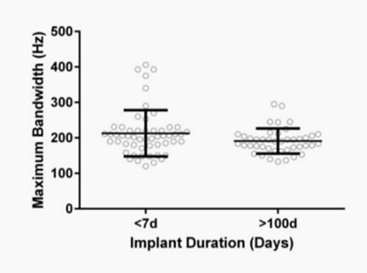

Opie等人进行了一系列实验,探讨了电极植入时间、位置和取向对支架电极带宽的影响。根据电极在导管内部署时所面对的方向,每隔45°放置一次电极。研究植入时间对带宽的影响,动物在植入两周后测量平均带宽为197.4±42Hz(对应于电极整合到血管壁的时间),20-28周时为194.4±20.8 Hz,信号质量没有明显下降。表1显示了描述剩余带宽随时间变化的数据。图5为长期电极植入前后信号采集的最大带宽的变化。

表 1 最大平均带宽、标准偏差和记录的信号范围,从动物植入支架高达190天

图5 植入运动皮层的电极阵列的最大带宽小于7天(n=4),且超过100天(n=6)